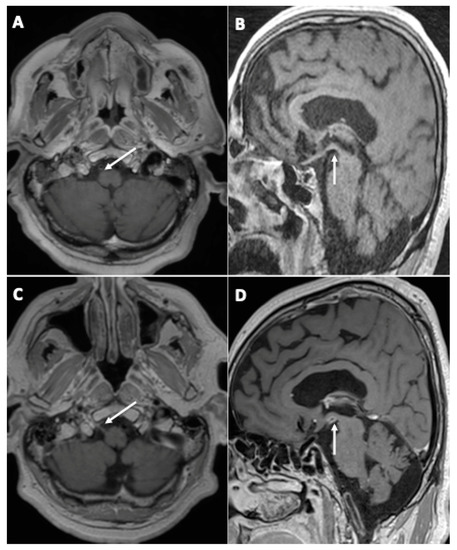

3.1. Brain MRI Findings

- Initial brain MRI findings

- Fourteen (45%) cases of focal (single focus or multiple foci) leptomeningeal enhancement (LME);

- Nine (29%) diffuse brain microhemorrhages, which predominantly involved the corpus callosum, the subtentorial juxtacortical WM, the internal capsule, the brainstem, the middle cerebellar peduncles, and the cerebellum, leading to the diagnosis of critical-illness associated cerebral microbleeds (CIAM) [14];

- Four (13%) acute ischemic strokes (acute small vessel infarcts or borderline infarction);

- Evolution of initial neuroimaging findings

- New findings during follow-up

- Evolution of perfusion imaging